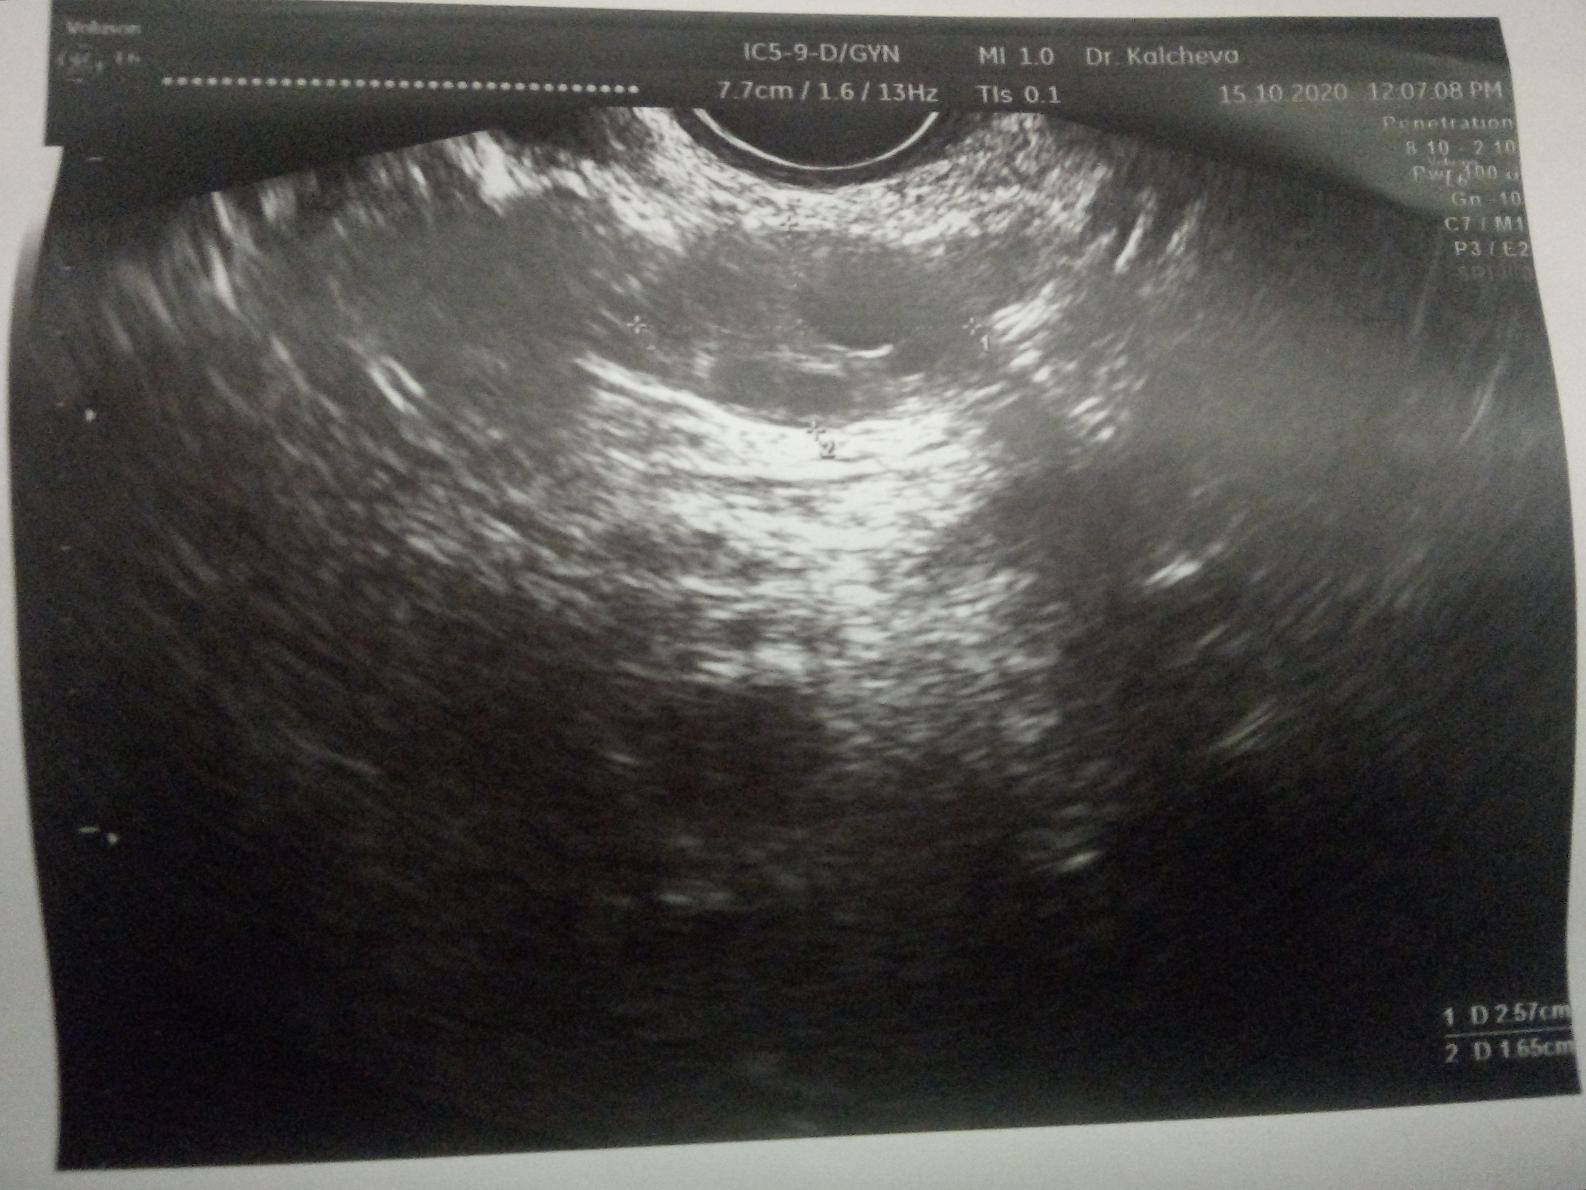

Първо да започна с това, че съм раждала. Детето ми е на 6 години и откакто родих от гърдите ми изтичаше капки "мляко" при стискане. Така 6 години. Един хирург ми каза, че не е нещо необичайно при раждали жени, отворени канали, затова и не го счетох за проблем. През това време съм нямала проблем с менструацията, овулацията и т.н. Последните 2 години бях "въздържала се" от сексуални контакти. Потънах в работа и отговорности, малко сън (понякога за 2 дни по 1-4 часа сън, дневни и нощни смени). Казвам го, защото мисля, че има отношения спрямо хормоните. Извинявам се, ако е излишна информация. След това, тази година имах момент на силна емоция. Съвпадна и със започването на нова работа. След това получих подуване на едната гърда, червенина, болка и на мястото на червенината затопляне. Помислих мастит и почнах Клиндамицин, но не изключвах най-лошия вариант. Ходих на ехограф на гърдите (бях се побъркала от мисли да не е рак на гърдата) - ехографията не показа нищо проблемно, т.е. освен запушена жлеза. След това с ехографията отидох при мамолог. Мамолога направи прегледа, видя ехографията и каза, че няма притеснително, но иска да изследвам пролактина, одобри и използването на Клиндамицина, от който всъщност ми мина гърдата. Нямах възможност да направя изследване на пролактина. След "сексуалната диета" и т.н. (дълга и широка) имах полов акт с любимия човек. 2-3 дни след това гърдите спряха да ми "сълзят" капки. Помислих, че всичко се нормализира вече. Бях изключила за датата ми на менструация и докато правихме секс ми дойде точно на датата, на която си ми идва - 27ми (това по-миналия месец). Месечния ми цикъл е от 29-30 дни, т.е. ми идва на същата дата всеки месец, най-много да ми подрани с 1 ден, но не закъснява. Октомви месец прокървях на 13-ти (по-точно полунощ на 12ти, затова казвам 13-ти). Първоначално беше кафеникаво, оскъдно зацапване. След 2 дни стана кафеникаво-червеникаво, пак леко течащо. Така до 16-17ти. Беше ми станало много лошо в първите дни, затова и потърсих един приятел да ме закара до болницата - виеше ми се свят и не бях сигурна в ходенето си (световъртежи и замаяност - имам мъдрец за изкарване, който явно е засегнал ухото, защото имах удебеляване леко зад ухото и като натиск, заради което почнах антибиотик Оспамокс 1000 и след него световъртежите минаха, но като го спрях седмица по-късно пак лека-полека почнаха, т.е. явно от зъба и трябва да го махна - първото, което ще направя). Та, ходих на гинеколог. Прегледа ме с вагинален ехограф по време на въпросното кървене (на 15-ти). Даде ми снимки. Каза, че нямам миоми, кисти и подобни. Че кървенето е на хормонална основа. На снимките се виждат фоликули (до колкото разбирам). Има малки с големина 1 см и нещо до 1 по-голям с размери близо до 5 см (явно доминантния фоликул). Каза ми "Когато сега ти дойде на датата, на която трябва, това в момента не го брой за менструация, на 2-3 ден от първия ден на менструацията направи изследвания на LH, FSH, Testosteron, Estradiol, Prolactin, а на 22-23 ден, считано от 1-я ден на менструацията на Progesteron. Това кървене е хормонален дисбаланс, който може да се дължи на стрес". След това бях с любимия човек от 21 до 24-ти Октомври, като може би беше 22-23ти, когато каза, че се е изтървал. Казах му, че не съм в овулация, не би трябвало, считайки, че когато кървях ми е била. Дойде 26-ти - няма менструация, 27-ми - няма менструация и така до ден днешен - от 27-ми Октомври чакам менструация, но няма. Днес е 11-ти ден закъснение, считано от 27-ми насам. Правих въпреки всичко тест за бременност за всеки случай на 30-ти Окт. и на 2-ри Ноември - и двата отрицателни. Имам един резервен за другата седмица (на Престо, отстана 2-рата касетка) и ако пак е отрицателен, то следва отново гинеколог или може би ендокринолог. Досега никога в живота ми не съм имала кървене между две менструации.

На първата снимка е по-големия фоликул. На втората ми се струва, че виждам 3 кисти в измерения, а каза, че нямам кисти, миоми и подобни.